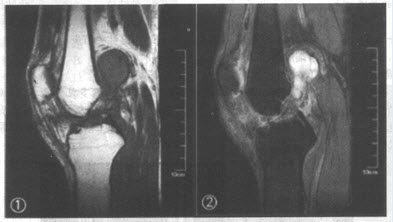

患者,女,65岁。左侧肢体偏瘫,言语不清2天入院,曾有高血压病史多年。影像学检查如下图。

(单选题)该患者的诊断是()

A:脑出血

B:脑炎

C:脑梗死

D:胶质瘤

E:脑脓肿

F:脑转移瘤